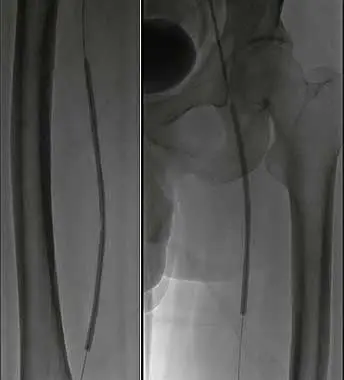

1、仰臥位,常規消毒鋪巾,2%利多卡因局麻。右股動脈穿刺入路,穿刺置管后,造影示:主動脈下段血流尚通暢,雙側髂總動脈輕度狹窄,髂外動脈及股總動脈血流通暢,右側股淺動脈、腘動脈輕度狹窄,左股淺動脈全程狹窄大于50%,中遠段閉塞約12cm。左腘動脈及雙側膝下流出道血流通暢。

2、建立通路換入6F長鞘,遠端位于左股淺動脈。配合導絲導管技術通過左股淺動脈狹窄閉塞段。

3、減容:交換V-18導絲,以6F Rotarex旋切導管于左股淺動脈閉塞處減容。

4、減容后,以SABER3mm*30cm球囊預擴張。

5、使用Matrix Super PTX (巴泰醫療)5mm*20cm及5mm*15cm約束型藥物涂層球囊全程擴張左股淺動脈病變。

6、復查造影見:左股淺動脈血流通暢,殘余狹窄小于 30%,左下肢血供明顯改善,撤出鞘管,封合器封合右股動脈穿刺點,安返病房。